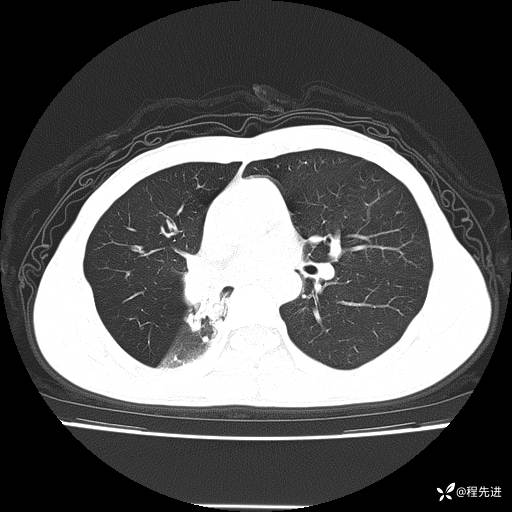

患者性别:男

患者年龄:49岁

主诉:咳嗽、胸痛1周

简要病史:1周前受凉感冒后开始出现咳嗽症状,阵发性连声咳,痰多,黄白痰,不易咳出,伴胸痛、气紧、胸闷,右侧为主,活动用力、呼吸时胸痛明显,曾在当地诊所贴敷膏药仍疼痛

体格检查:T:36.3 ℃ P:80 次/分 R:20 次/分 BP:120/88 mmHg,指脉氧饱和度97%,意识清晰,呼吸平稳,右侧第二、三肋骨压痛,可见膏药贴敷,皮肤无异常,双肺呼吸音粗,未闻及干湿性啰音。心率80次/分,节律整齐,无杂音。腹平软,全腹无压痛无反跳痛

临床诊断:社区获得性肺炎

CT平扫: